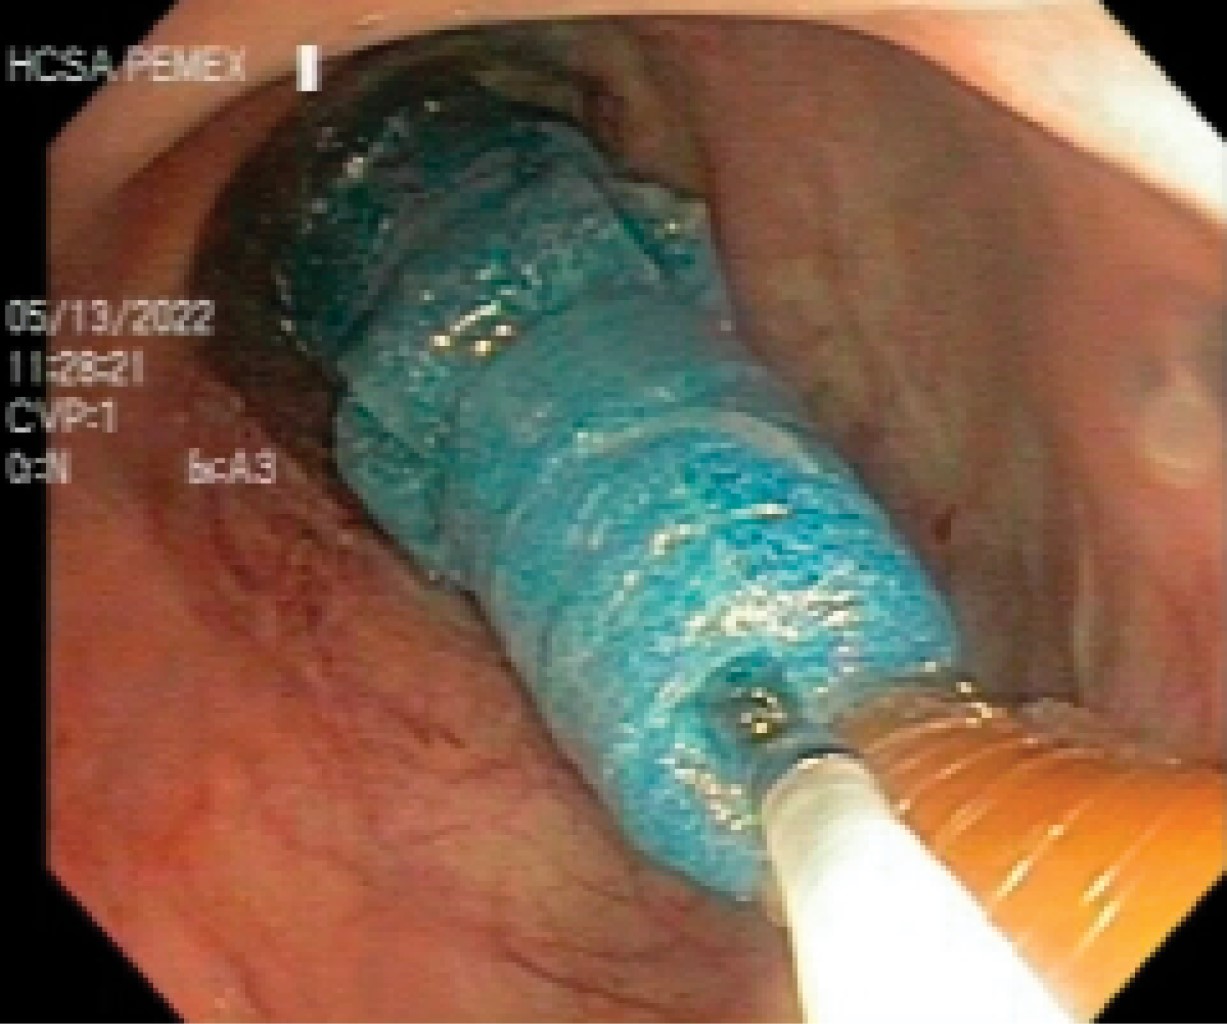

Figure 2